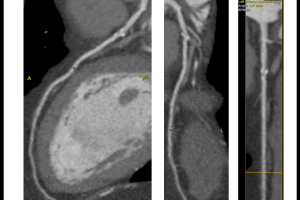

Šta je MSCT koronarografija?

MSCT koronarografija je brza, precizna i neinvazivna metoda snimanja koja nam omogućava jasan uvid u stanje vaših koronarnih arterija. Pomoću najsavremenije CT tehnologije, možemo detaljno analizirati protok krvi i identificirati eventualna suženja ili blokade.

3. Precizna dijagnostika: Najsavremenija tehnologija omogućuje nam otkrivanje čak i najmanjih promjena u koronarnim arterijama.